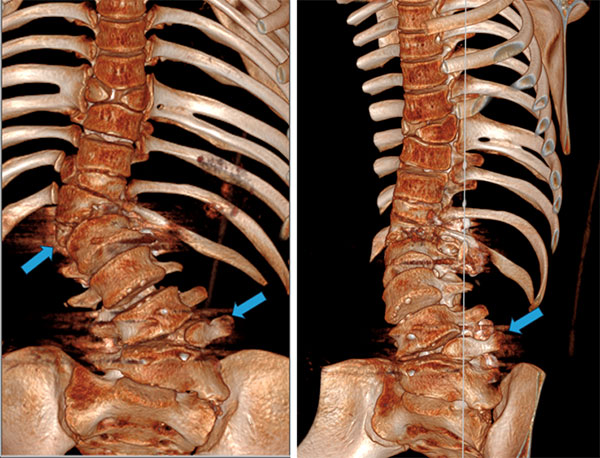

孩子父母走访多地寻医问药,恰逢脊柱外科陈崇博士在佛冈县人民医院帮扶,来到陈崇博士门诊寻求帮助。陈崇博士等详细分析了病情,主要的技术难点有三,其一是从影像学资料来看,患者是复杂的先天性脊柱畸形,不仅有多个半椎体,同时还有不对称发育的蝴蝶椎、肋骨畸形等;其二,已发展至严重的冠状面及矢状面的失平衡;其三,翻修手术,尤其是脊柱畸形的翻修手术,术中解剖结构不清晰,往往充满了许多不确定性,且原有的半椎体已经生长发育成熟,体积较大,切除风险较高。

术前通过广东省人民医院三维打印实验平台,制定个体化治疗方案,发现患者已经出现部分腰骶及上胸段代偿性弯曲,如不及时纠正,畸形会继续加重以及神经功能持续恶化,手术矫形是当前唯一的治疗方式。

为了保证孩子的生活质量、腰椎的活动度且又要达到良好的矫形效果,这是一个巨大挑战及考验。手术方案设计为拆除原有的两处脊柱内固定,切除致病的“恶性”半椎体,充分松解,再后路O臂导航下进行椎弓根螺钉固定矫形,对两处内固定中间地带,不进行融合、固定。